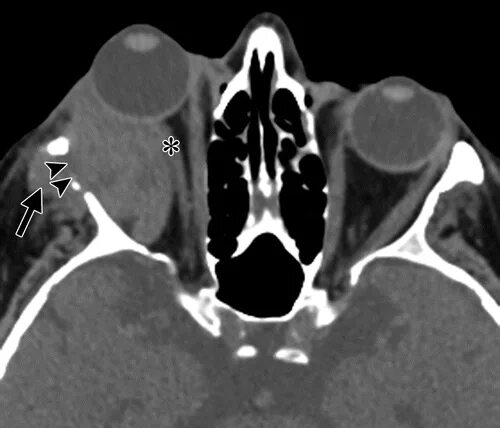

Плохо после контраста кт